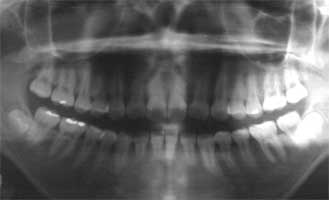

Fig. 14 Ms F 17 years later 33 years old.

As a result of continuing monthly maintenance the possibility of advancement of gingivitis has not occurred.

Ms F 16 years old at the time of the first medical examination. Woman (Fig. 13-14)

She has undergone gingivitis treatment two years ago. However a lot of tartar of the edge of the gum was found on her teeth at the time of first medical examination. Her 5 year older sister already had a tooth in the final stage of gingivitis. Ms F therefore had the strong possibility of also developing to the final stage. Taking note of this I believed her to be of juvenile gum disease. As a result of consistently continuing to remove the tartar her tendency to develop gingivitis has not occurred even 17 years later. Even her older sister who lost a tooth to gingivitis, 16 years later has maintained and retained all other teeth.